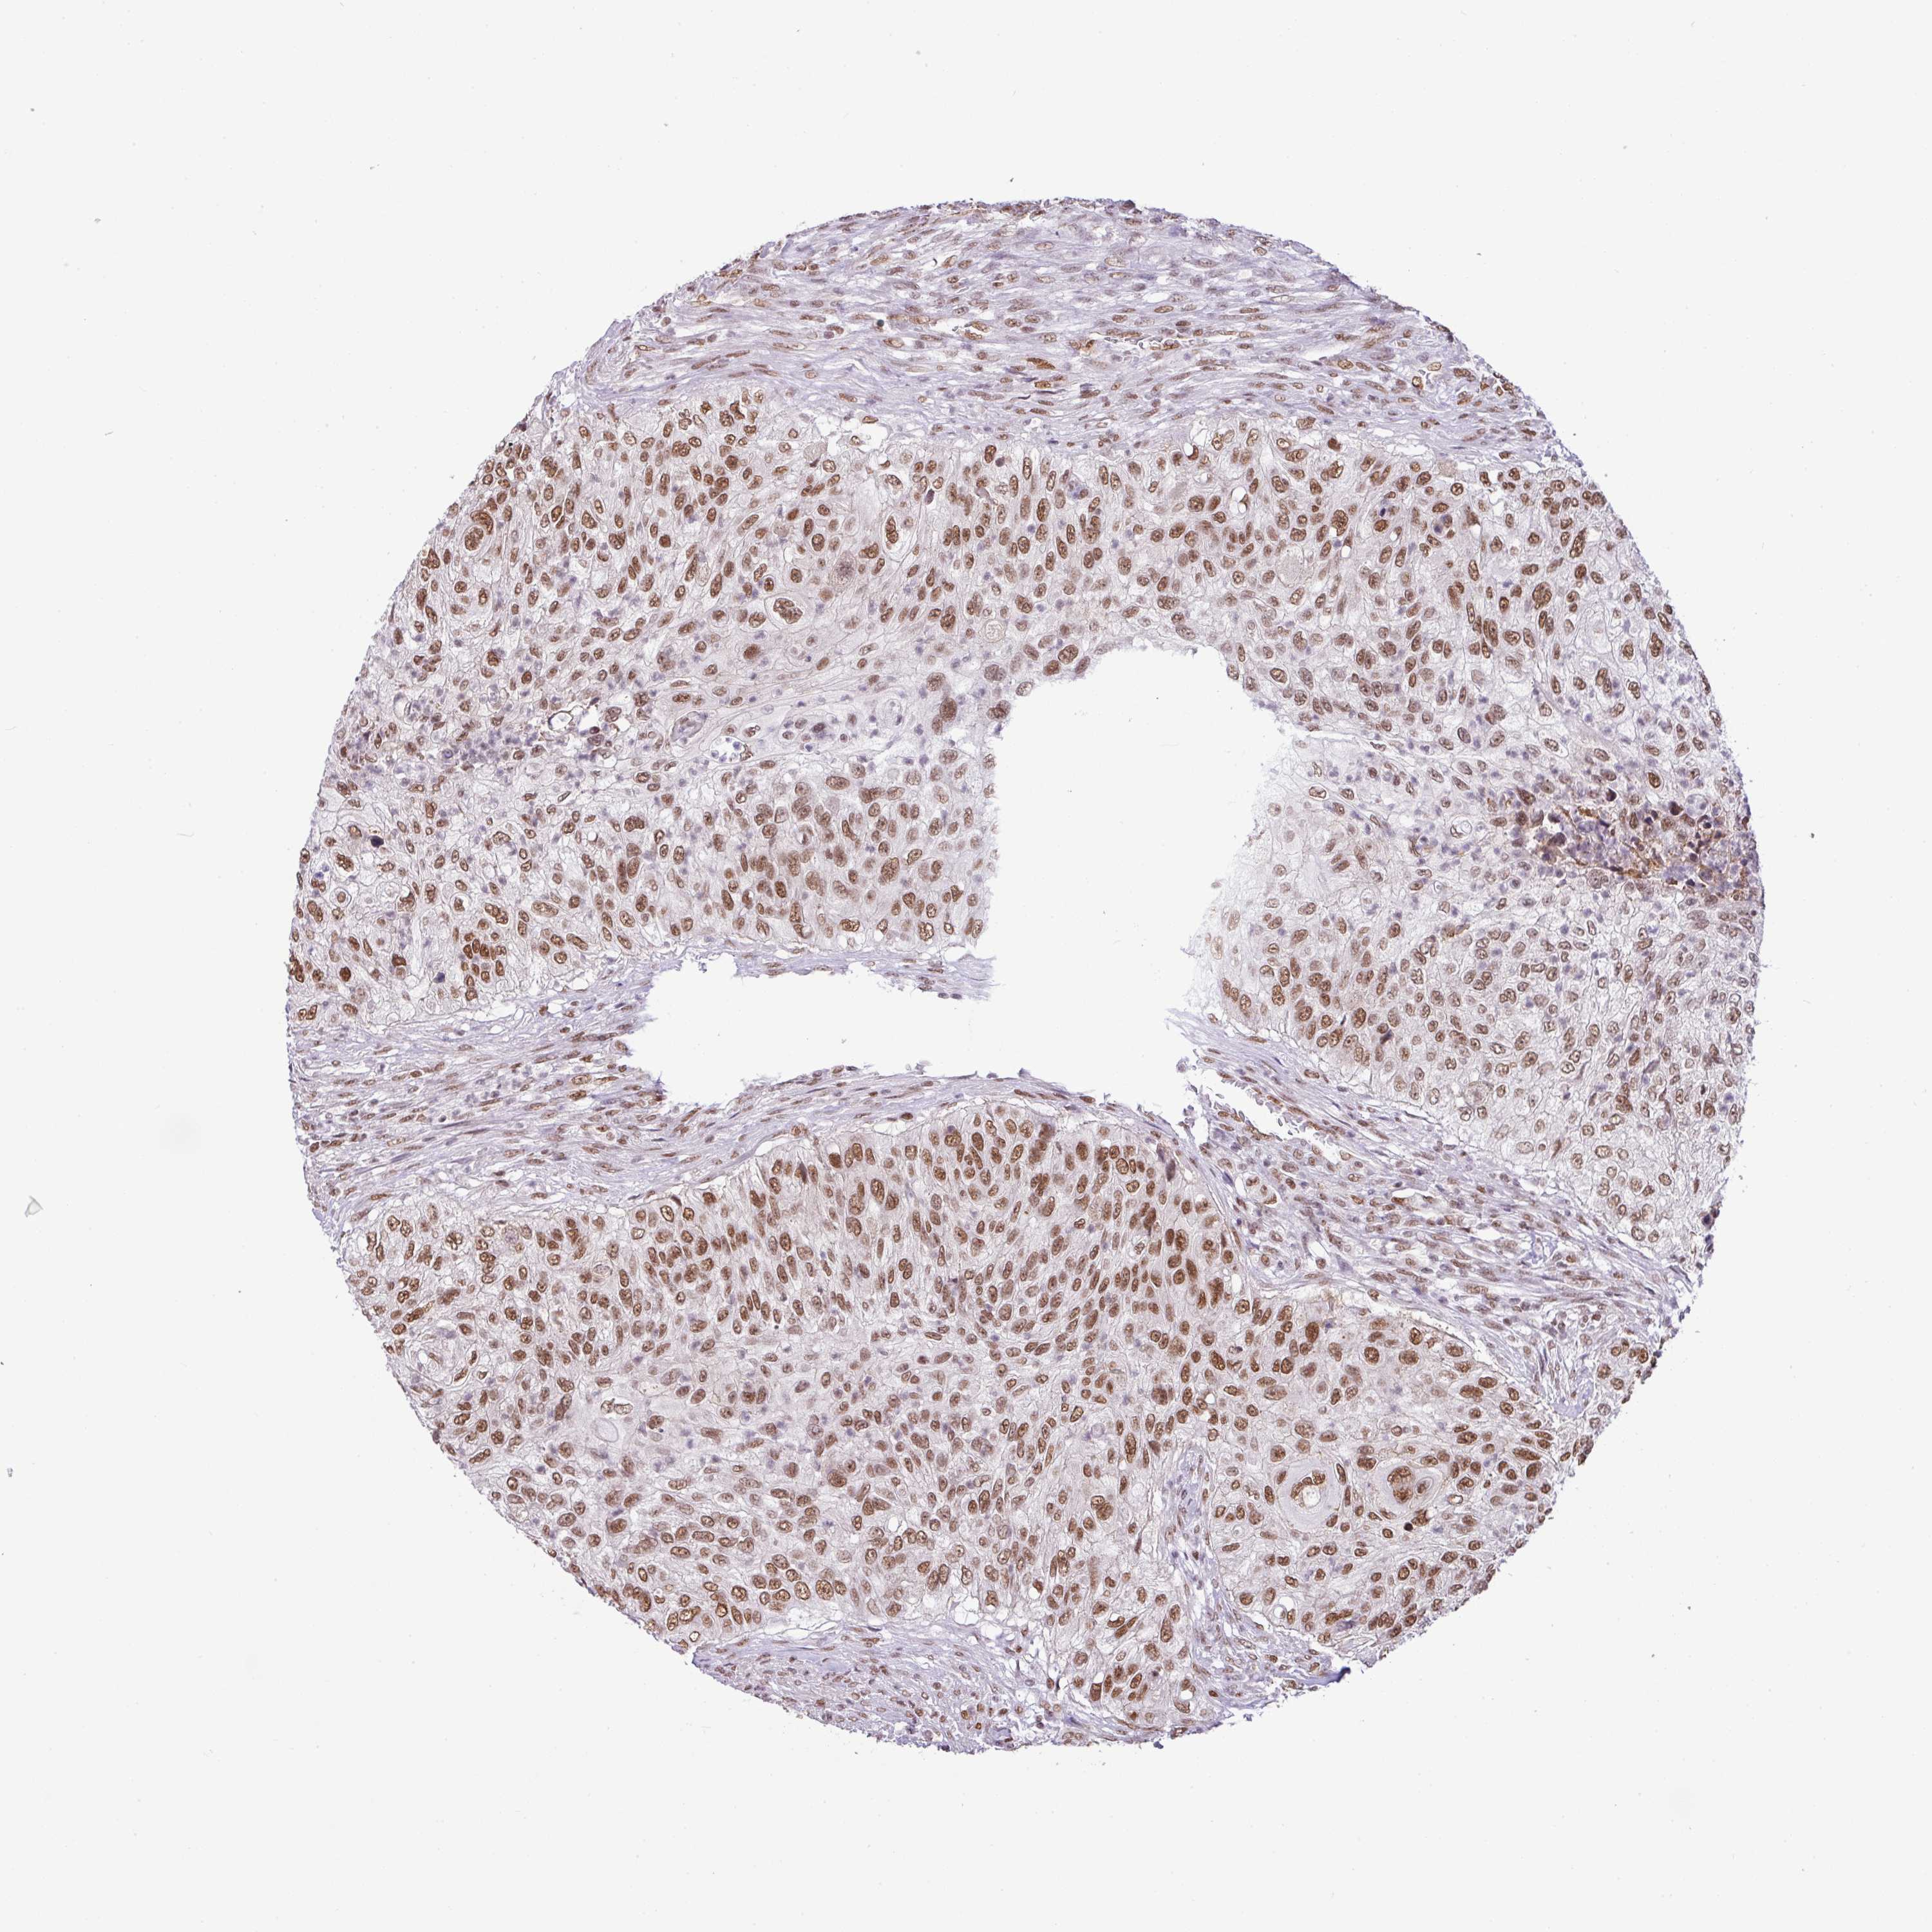

UROTHELIAL CANCER - Protein expressioni

A mouse-over function shows sample information and annotation data. Click on an image to view it in a full screen mode. Samples can be filtered based on level of antibody staining by selecting one or several of the following categories: high, medium, low and not detected. The assay and annotation is described here.

Note that samples used for immunohistochemistry by the Human Protein Atlas do not correspond to samples in the TCGA dataset.

Antibody stainingi

Antibody staining in the annotated cell types in the current human tissue is reported as not detected, low, medium, or high, based on conventional immunohistochemistry profiling in selected tissues. This score is based on the combination of the staining intensity and fraction of stained cells.

Each image is clickable and will lead to virtual microscopy that enables deeper exploration of all samples and also displays staining intensity scores, fraction scores and subcellular localization as well as patient and tissue information for each sample.

Antibody HPA011318

Antibody HPA054041

Staining

High

Medium

Low

Not detected

Intensity

Strong

Moderate

Weak

Negative

Quantity

>75%

75%-25%

<25%

None

Location

Nuclear

Cytoplasmic/membranous

Cytoplasmic/membranous,nuclear

Urothelial carcinoma, High grade

Urothelial carcinoma, NOS

Urothelial carcinoma, Low grade